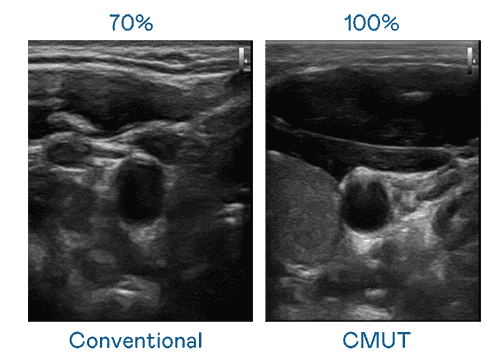

CMUT 技术是一种用电容式微机电元件来产生超音波讯号的技术。。与传统 PZT 压电式技术相比,,,CMUT 频宽增加 30%,,,更宽频的超音波讯号让影像解析度大幅提升,,,是实现高影像品质医疗超音波扫描、、、、促进精准医疗发展的关键技术。。

大频宽带来超清晰影像

超音波影像的解析度高低,,,首先取决于探头能发出的讯号频宽。。。彩神vll CMUT 可提供高清晰的超音波讯号,,,,提供高频宽、、、、高灵敏度、、、、影像纹理细节更高的超音波影像,,,协助医护人员缩短影像判读时间及利用精准的医疗影像进行诊断。。。。